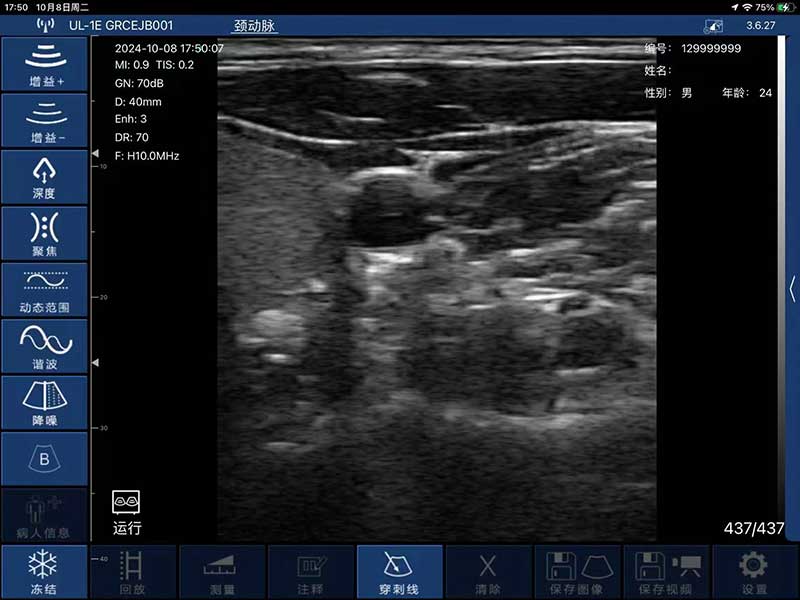

- Display mode: B, B/M, B+Color, B+PDI, B+PW

- Probe frequency: 7.5MHz/10MHz

- Scan depth: 20/40/60/80mm

- Scan width: 40mm

- Cineplay: auto and manual, frames can set as 100/200/500/1000

- Puncture assist function: the function of in-plane puncture guide line, out-of-plane

puncture guide line, automatic blood vessel measurement.

- Image frame rate: 18frames/second